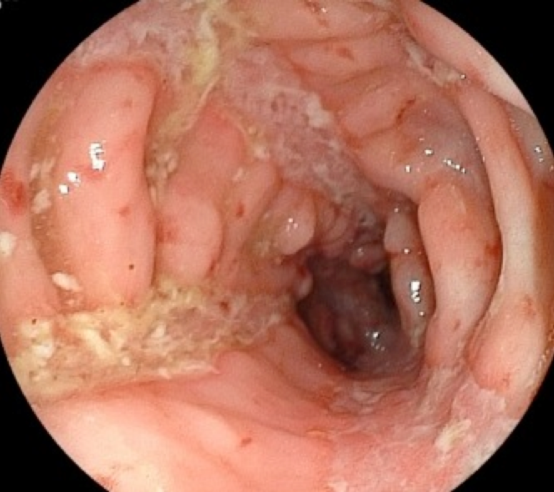

大腸内視鏡検査における縦走潰瘍および敷石像

大腸型クローン病患者の結腸において、数条の縦走潰瘍と、その周りに敷石像を認める。